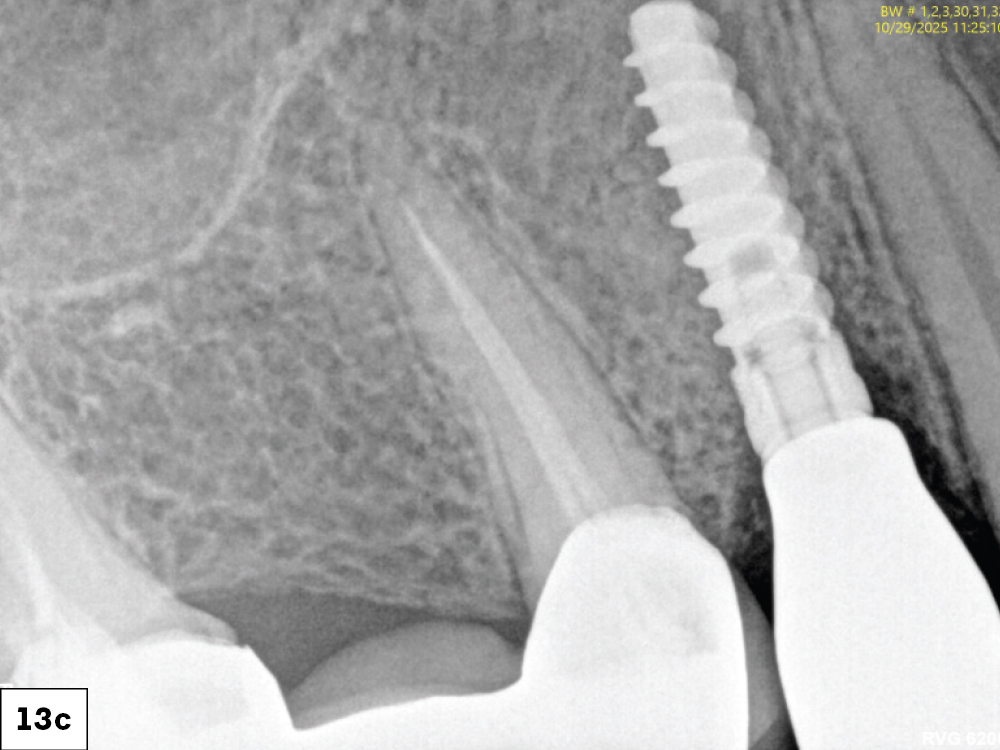

At eight weeks, mature keratinized mucosa framed the zirconia crowns with stable crestal bone levels and ideal emergence profiles were confirmed radiographically-c

At eight weeks, mature keratinized mucosa framed the zirconia crowns with stable crestal bone levels and ideal emergence profiles were confirmed radiographically-d

Figures 13a–13d: At the one-week follow up, both implants demonstrated excellent integration with healthy peri-implant tissues and no inflammation. At eight weeks, mature keratinized mucosa framed the zirconia crowns with stable crestal bone levels and ideal emergence profiles were confirmed radiographically.